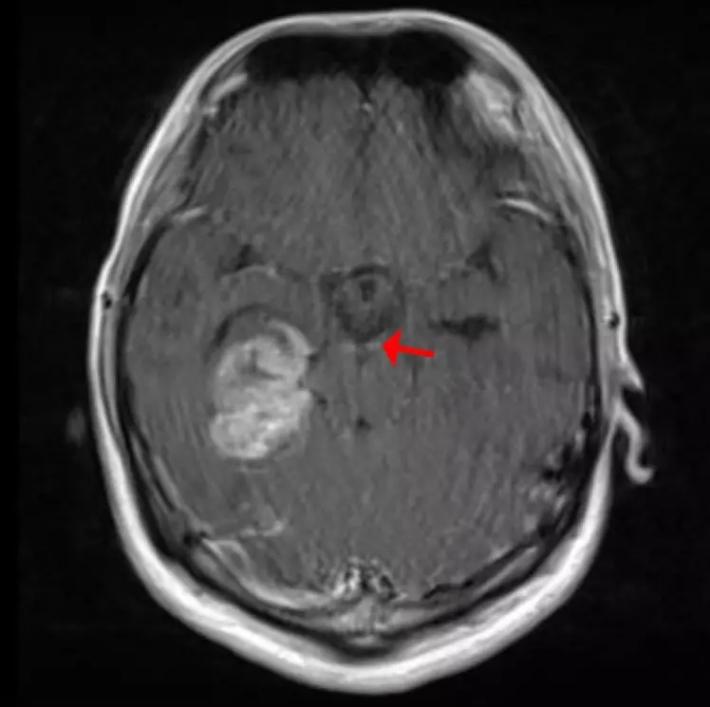

图7. 头颅 MRI:1. 右侧海马异常强化影,部分软脑膜播散转移可能。 2.幕上脑积水伴间质性水肿。 3.左侧额顶枕叶、右侧丘脑及侧脑室旁新发梗塞灶考虑。 第二次MDT讨论: 结合最近的MRI报告、脑脊液脱落细胞结果,证实患者胶质瘤经脑脊液及软脑膜播散。同时回顾病史及患者第一次术前MRI表现,右侧海马病灶无法解释双下肢的症状(排除癫痫),而脑干软脑膜上可见部分点状增强病灶(图8),因此考虑患者术前已存在肿瘤播散。目前治疗首先考虑通过脑室-腹腔分流解除颅内高压。待一般条件允许时考虑行进一步放、化疗。

图8.术前增强头颅MRI。红色箭头示脑干周围点状增强病灶为可能的播散病灶。